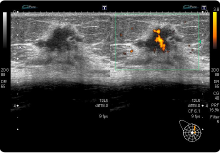

乳腺超音波

体にゼリーを塗り超音波の出る機械を当てて、病気を見つけます。触っても分からない小さいしこりも見つけることができます。当院ではフルデジタルの超音波装置を用いており、病変の形状や内部構造など乳がんの診断に必要な情報を得ることが出来ます。